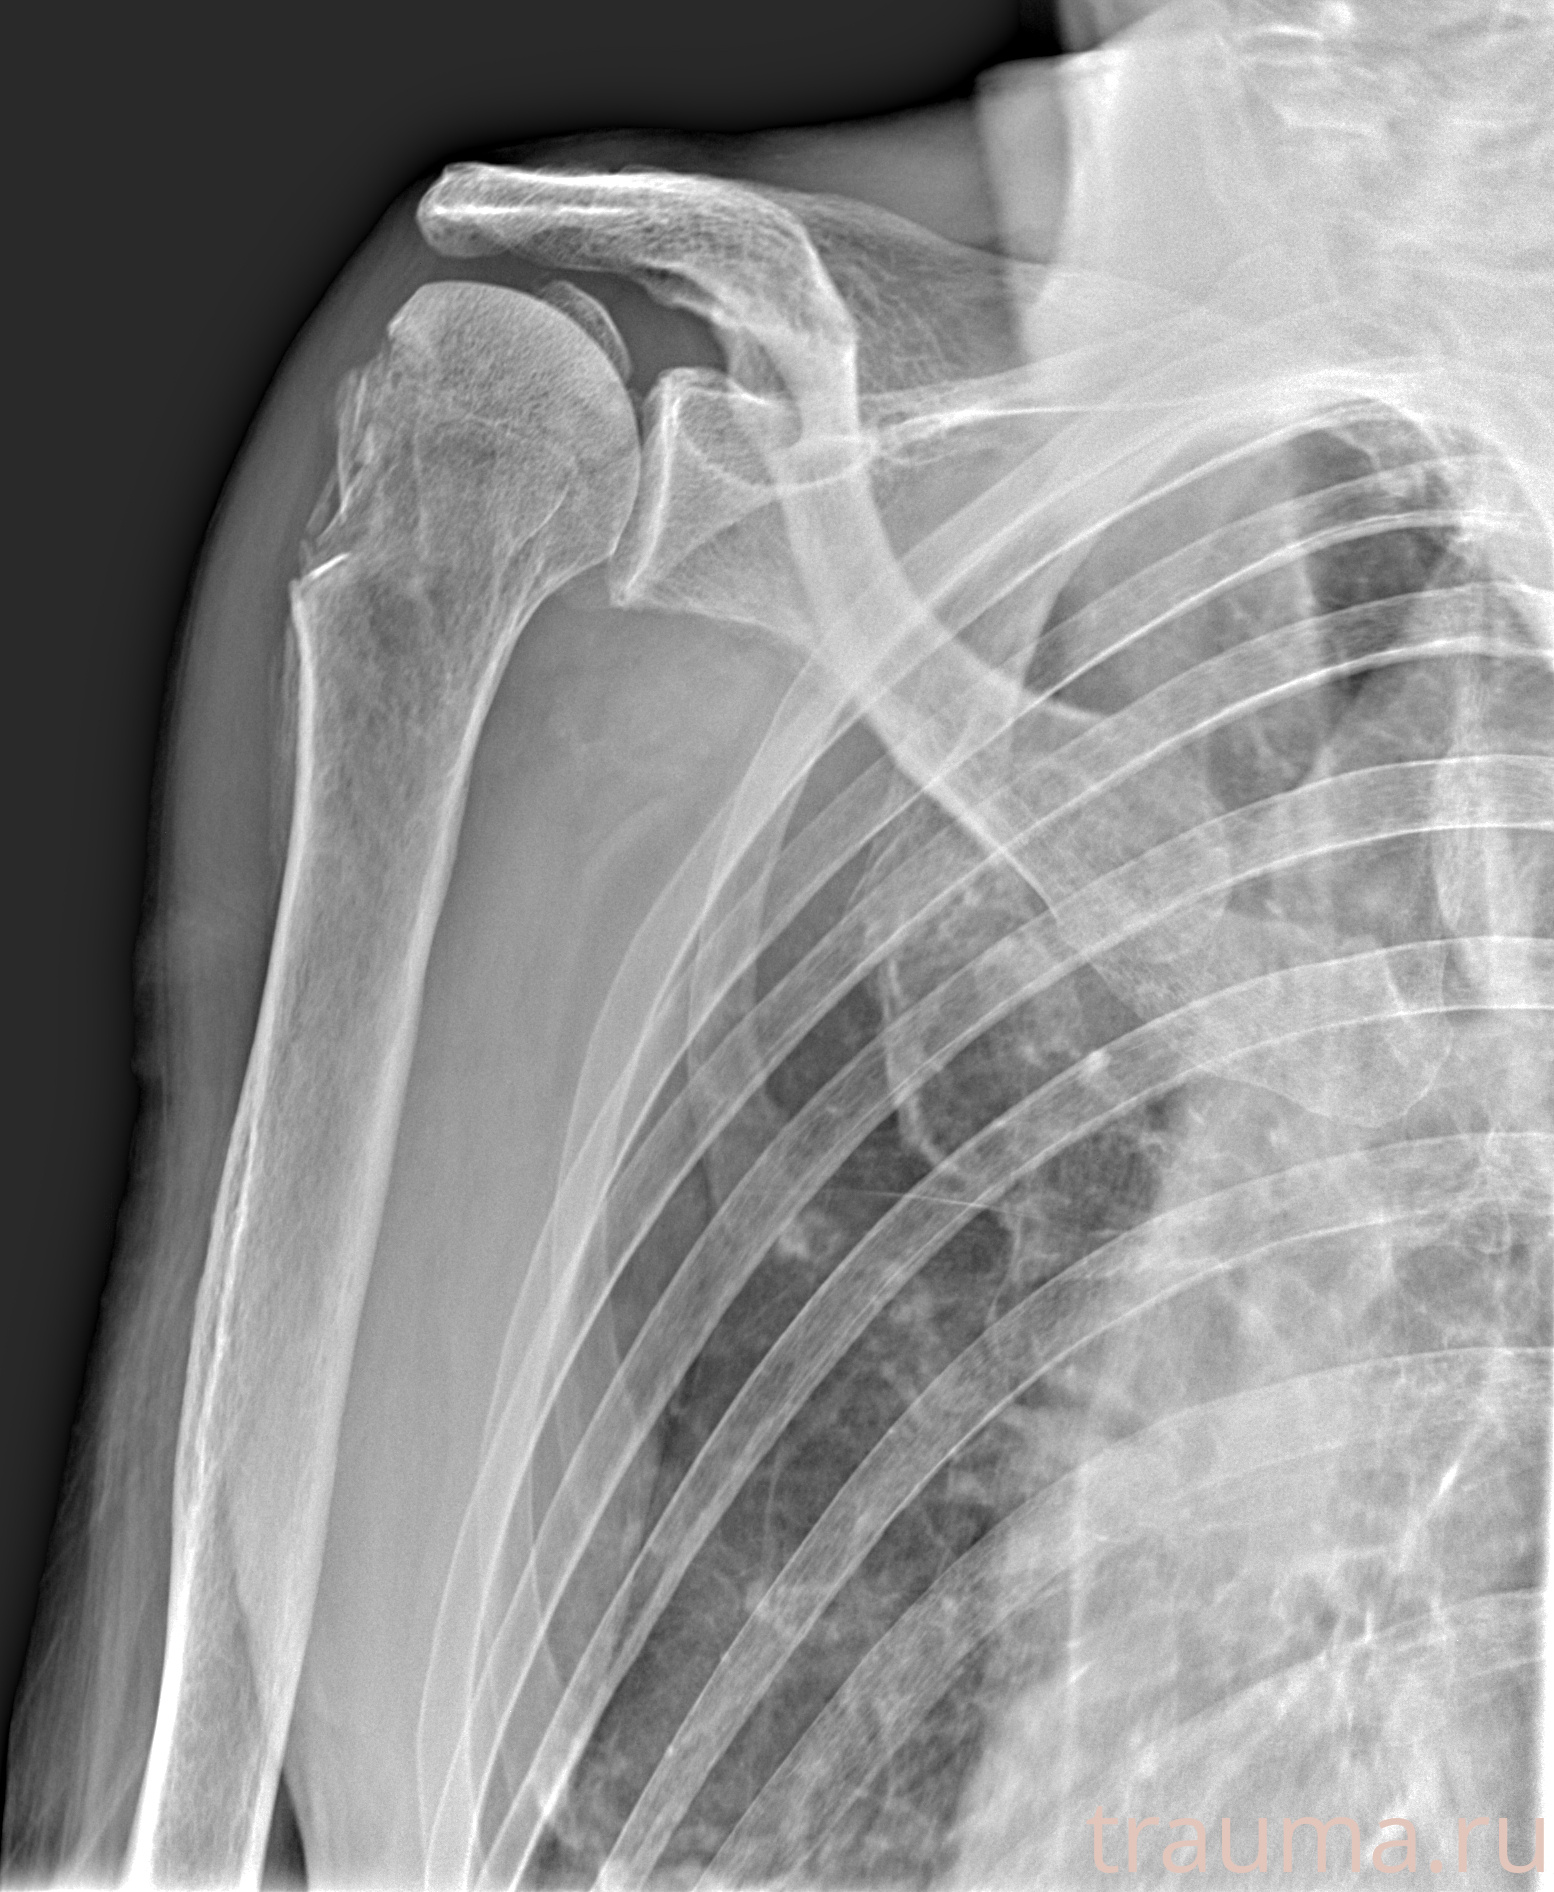

Рентгенограммы

Рентген на дому: по вашему адресу приезжает врач-рентгенолог, травматолог-ортопед с мобильным рентгеновским аппаратом, проводит диагностику травмы или заболевания, делает необходимые рентгенограммы, дает рекомендации по дальнейшему лечению. Получить качественные снимки в домашних условиях возможно благодаря уникальной методике, разработанной МосРентген Центром для института  Склифосовского